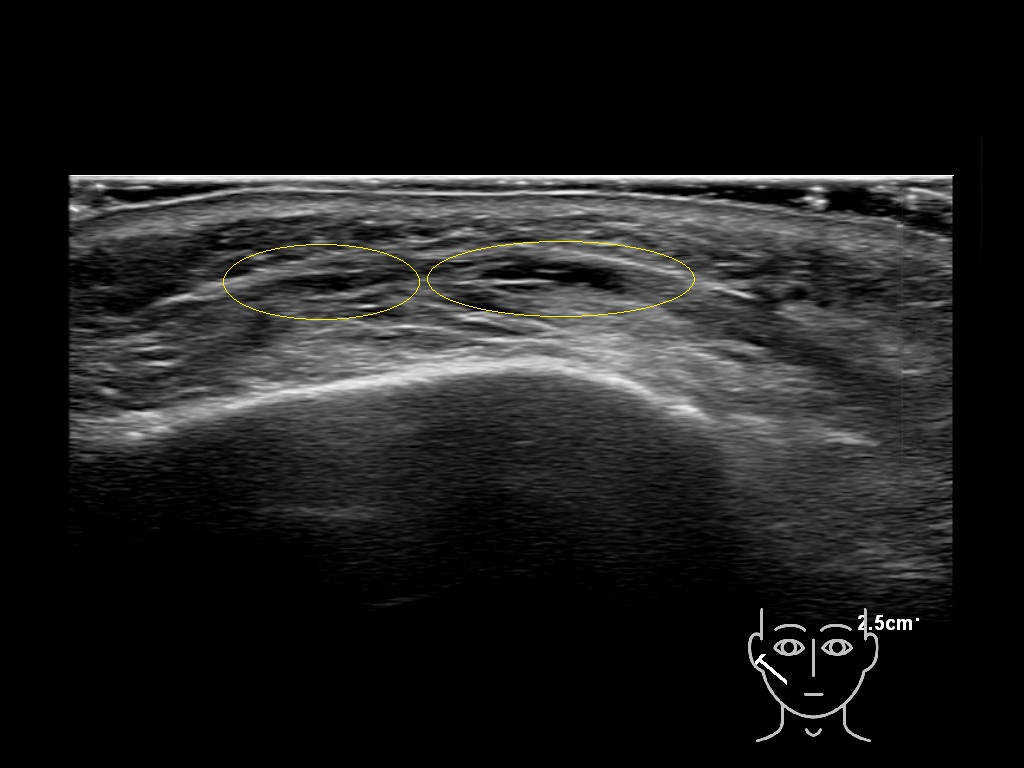

Filler deposits may end up unintentionally in the SMAS or fascial layers of the skin. Very often this will not lead to adverse events, however, adverse events ( nodules, migration / redistribution impaired muscle movement and smiling and malar edema) are are often related to filler ending up in the SMAS or fascia.

Study the first image to recognize the different layers. If you are sure about the layers, swipe to the second image to view the answer (if applicable).